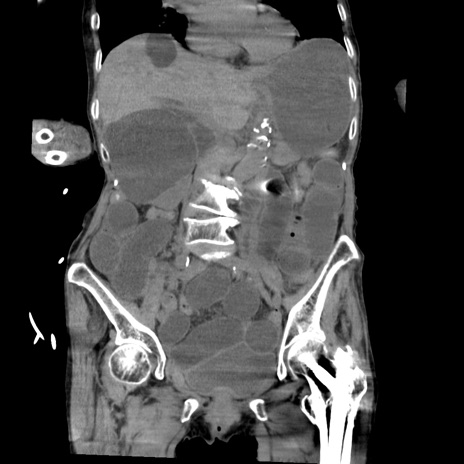

症例27(冠状断像)

【症例】80歳代女性

【主訴】嘔吐、腹痛

【現病歴】数時間前より嘔吐あり。心窩部痛出現し、徐々に右下腹痛あり。その後も数回嘔吐あり救急搬送となる。

【既往歴】左大腿骨頚部骨折手術

【身体所見】腹部は膨隆しているが軟らかく圧痛なし。腸雑音はやや亢進。

【データ】WBC 12000、CRP 19.05